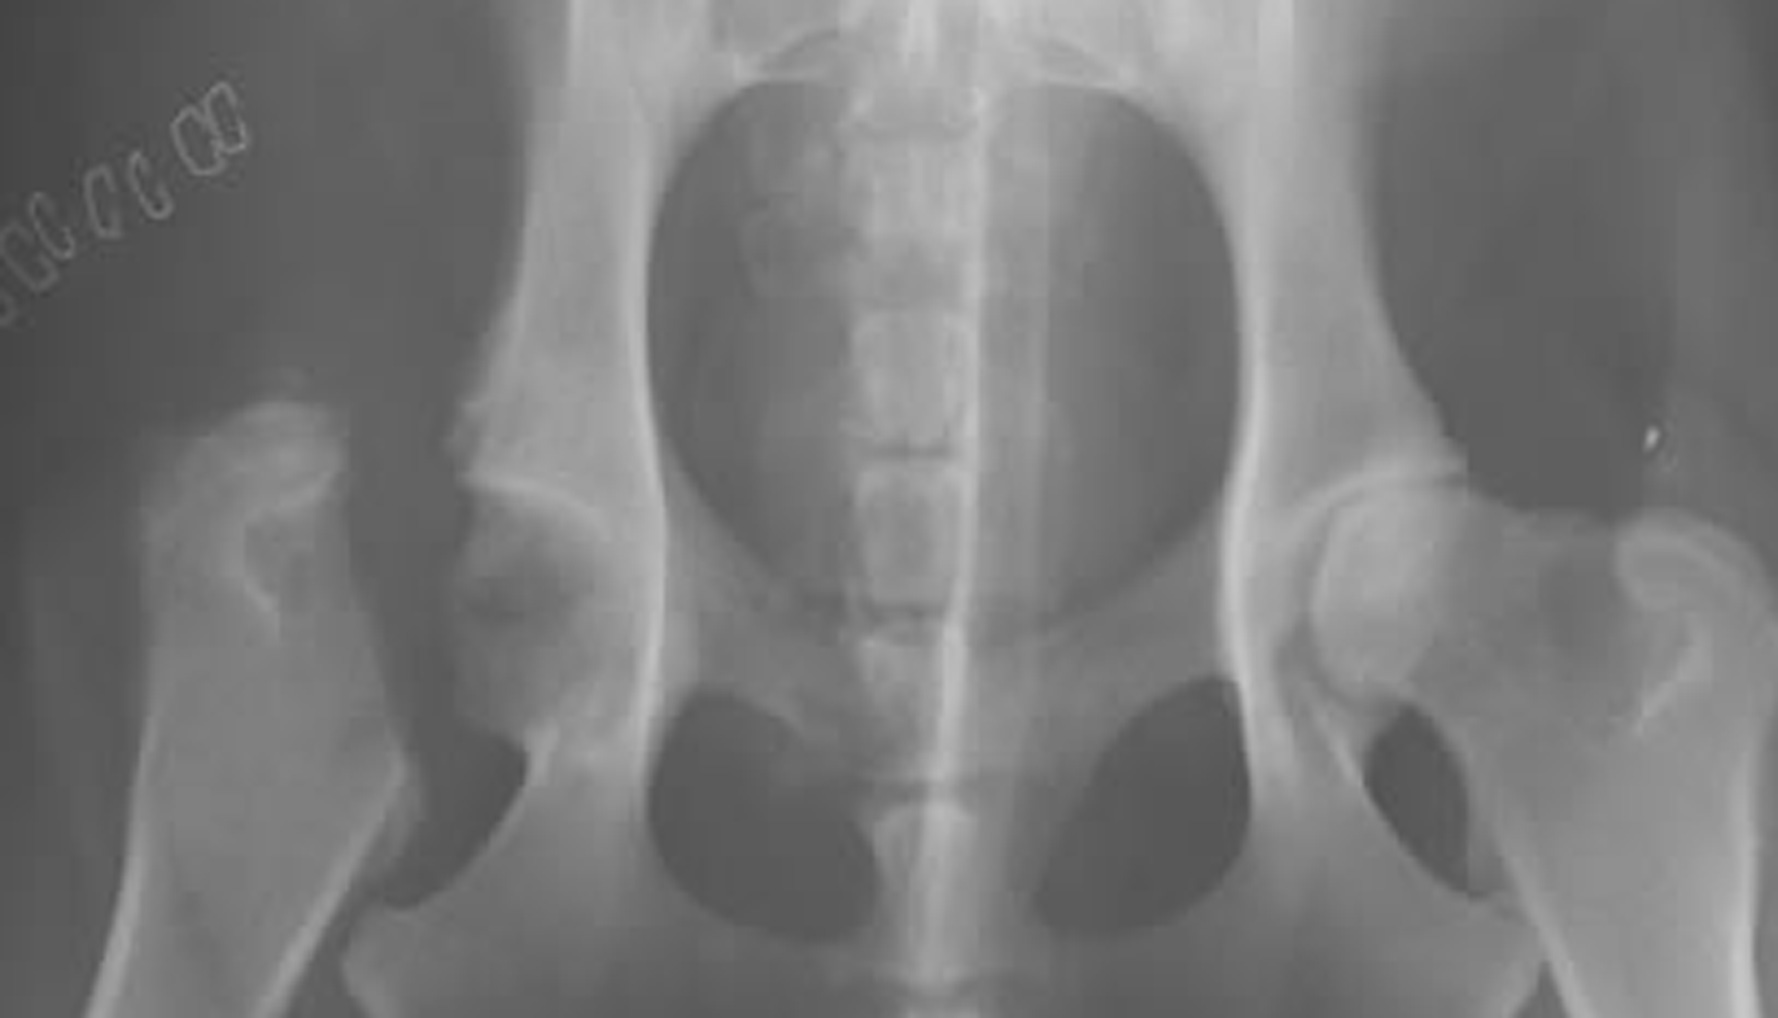

FHO Surgery

During the FHO surgery, the surgeon will remove the femoral head leaving the socket portion of the hip empty. Your dog's leg muscles will initially hold the femur in place as scar tissue develops between the femur and acetabulum.